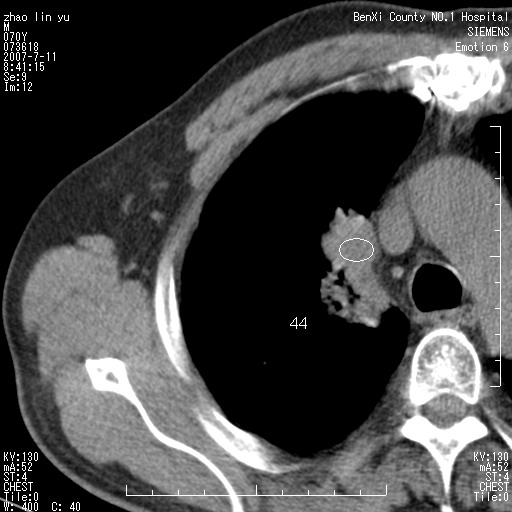

以下是引用王靖旗在2007-7-10 17:12:00的发言:[br] 男、70、咳嗽两个月,半年前换瓣手术,胸片未见异常,于昨天行x片发现右肺上野大片影,行ct扫描,这里是减薄图像,余肺正常。明天晚上会有增强扫描片,到时我会上传。[br][br] 冠状位请大家细看,应该是有意义的,[br][br] 请大家先看平扫发表意见。[br][br]

以下是引用zhangzhongshou在2007-7-10 21:43:00的发言:[br]右肺上叶周围型肺癌,以孤立型细支气管肺泡癌可能性大。